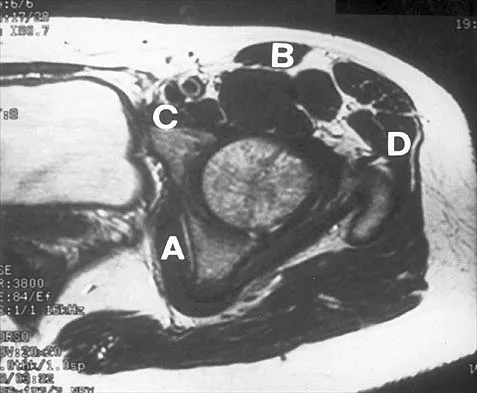

Figure 37 shows the T2-weighted MRI scan of the hip joint. What structure is labeled A?